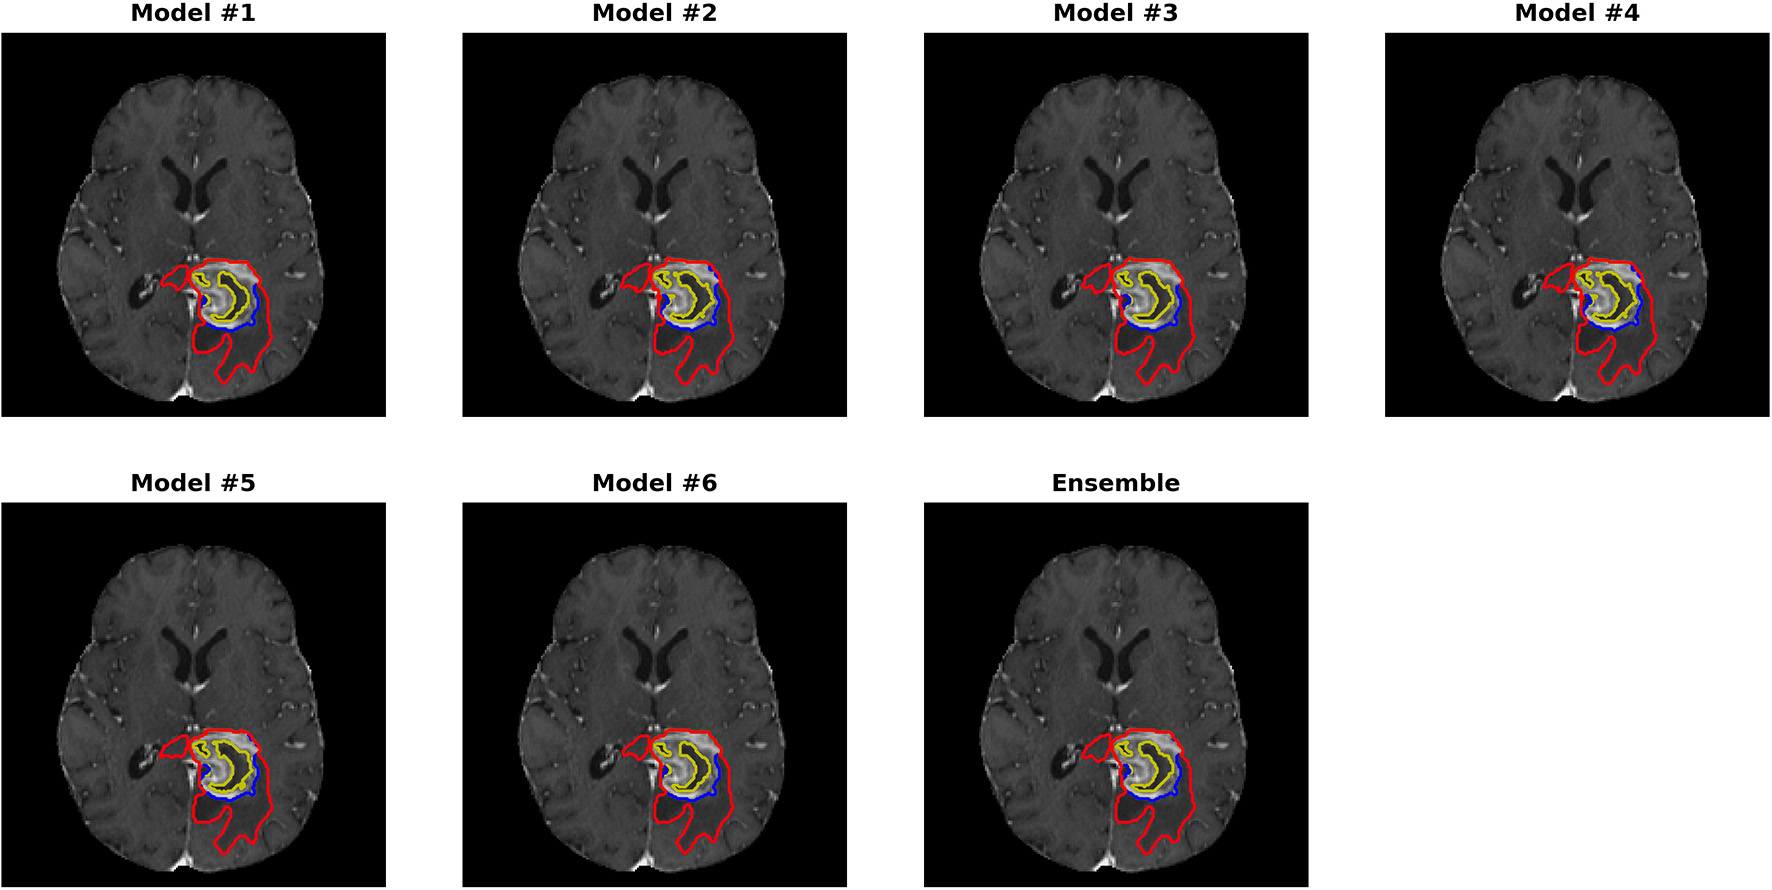

Figures 3, 4 show two slices (axial slice 76 and 81) of the automatically segmented labels overlaid on the T1Gd and T2 images, respectively. The showed case was “Brats18_CBICA_BHF_1” and was randomly selected from the validation dataset for demonstration. A single model may suffer from under- or over-segmentation while the average of multiple models achieves a more stable performance, which is also closer to the ground-truth, as shown with the improved Dice scores. Furthermore, the ensemble of all 6 models yields a much smoother boundary for different sub-regions and eliminates a few isolated regions, which are likely false positives.

Figure 3. Automatically segmented sub-regions from models 1–6 and the ensemble model. The underlying image is the corresponding T1Gd from the validation case “Brats18_CBICA_BHF_1.” Red, yellow and blue delineate the predicted boundaries of the total tumor, enhanced tumor core, and peritumoral edema, respectively.

FIGURE 4

www.frontiersin.org

Figure 4. Automatically segmented sub-regions from model 1–6 and the ensembled model. The underlying image is the corresponding T2 from the validation case “Brats18_CBICA_BHF_1.” Red, yellow and blue delineate the predicted boundaries of the total tumor, enhanced tumor core, and peritumoral edema, respectively.